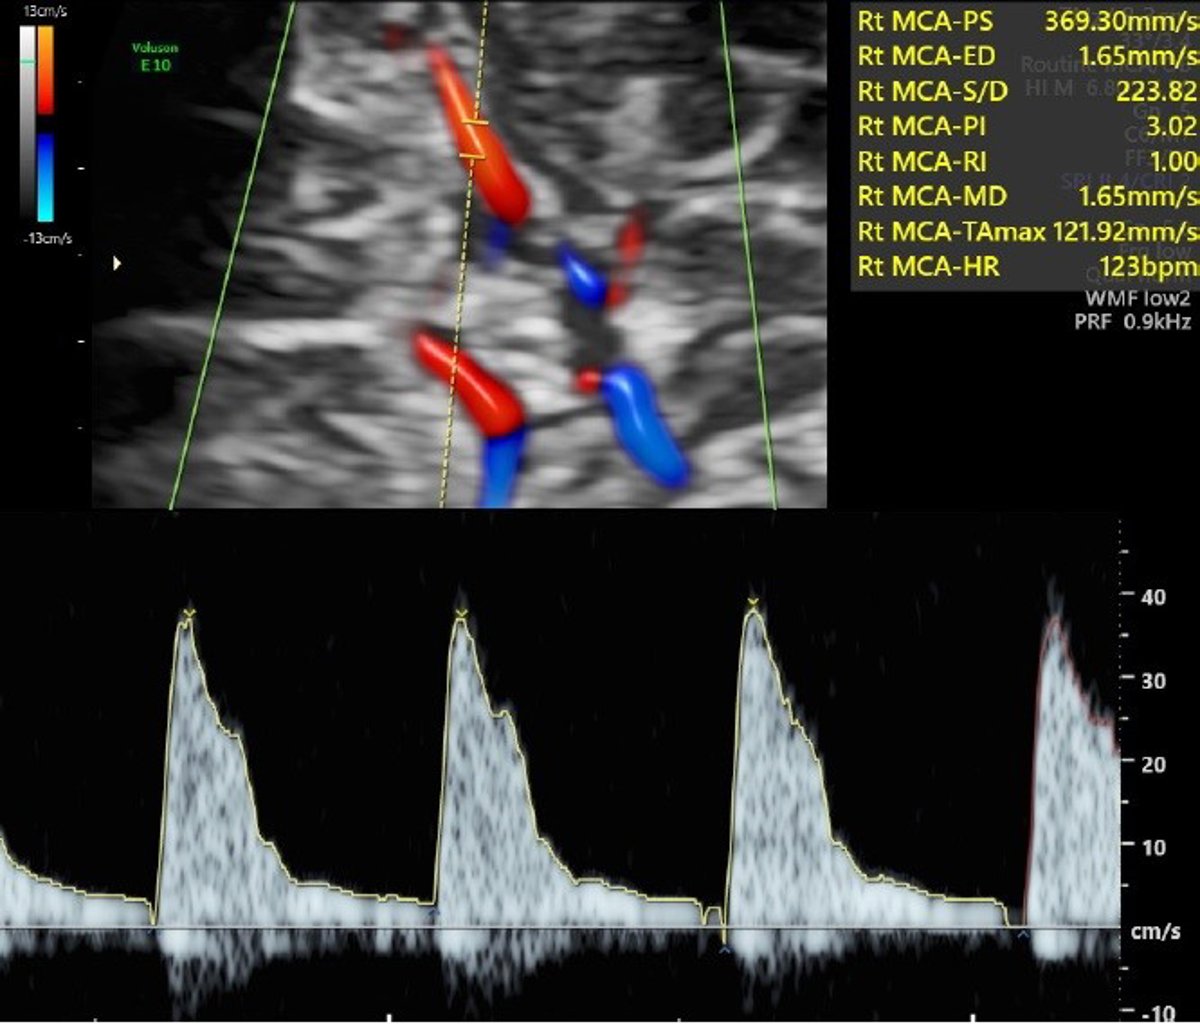

Una prueba con ecografía Doppler, que mide la circulación de la sangre por el cordón umbilical y el cerebro, denominada ratio cerebro-placentario (RCP), puede detectar la insuficiencia placentaria, pero hasta ahora la prueba solo se realizaba en embarazos con problemas, en casos muy indicados.

En la ecografía de las 36 semanas se midió el RCP en todas las mujeres, pero las participantes fueron divididas al azar en dos grupos: en unas, la prueba se usaba para cambiar el manejo de la gestación y, en caso de salir alterada, se proponía a la mujer una inducción precoz del parto al llegar al término; y en las otras, el resultado de la prueba no se comunicaba y se manejaba el embarazo según los protocolos vigentes.